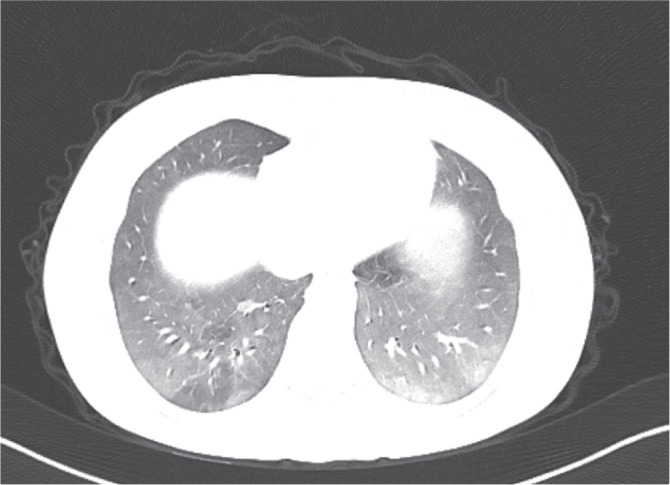

Everolimus is one of the immunosuppressive drugs used in solid organ transplantation. Many side effects have been described for these immunosuppressive drugs, similar to other drugs in this category. The purpose of this case presentation is to draw attention to drug-induced pneumonitis, which is a rare and life-threatening side effect of everolimus. A nineteen-year-old female patient who received liver transplantation for toxic hepatitis was admitted to our institute with cough and dyspnea. Everolimus had been started in conjunction with tacrolimus therapy 6 months prior to admission. Her chest imaging were consistent with pneumonitis. Markers of infection and cultures were all negative. After discontinuation of everolimus, symptoms and radiological findings resolved. The adverse effects of the drug should be kept in mind while investigating possible infectious agents in liver transplant recipients who are prone to opportunistic infections.

Abstract Image